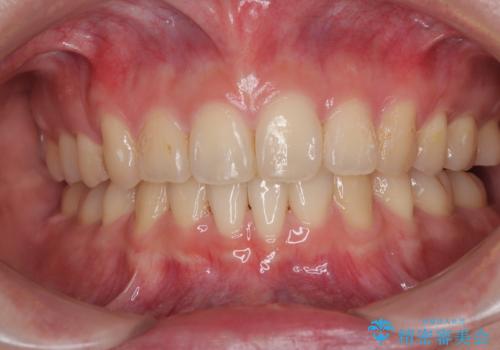

- 下顎の前歯が上顎の歯肉に咬みこむくらいに突出した上顎前歯を気にして来院された患者様です。

口元の突出感はないものの、上顎前歯が前方に傾斜して突出しており、前後に大きなズレがあり非常に深い咬み合わせとなっていました。

深い咬み合わせは上顎前歯を引っ込ませる大きな障害となるため、咬み合わせの改善が非常に重要となります。やや期間はかかりましたが、当初狙った通りの仕上がりで治療を終えることができました。